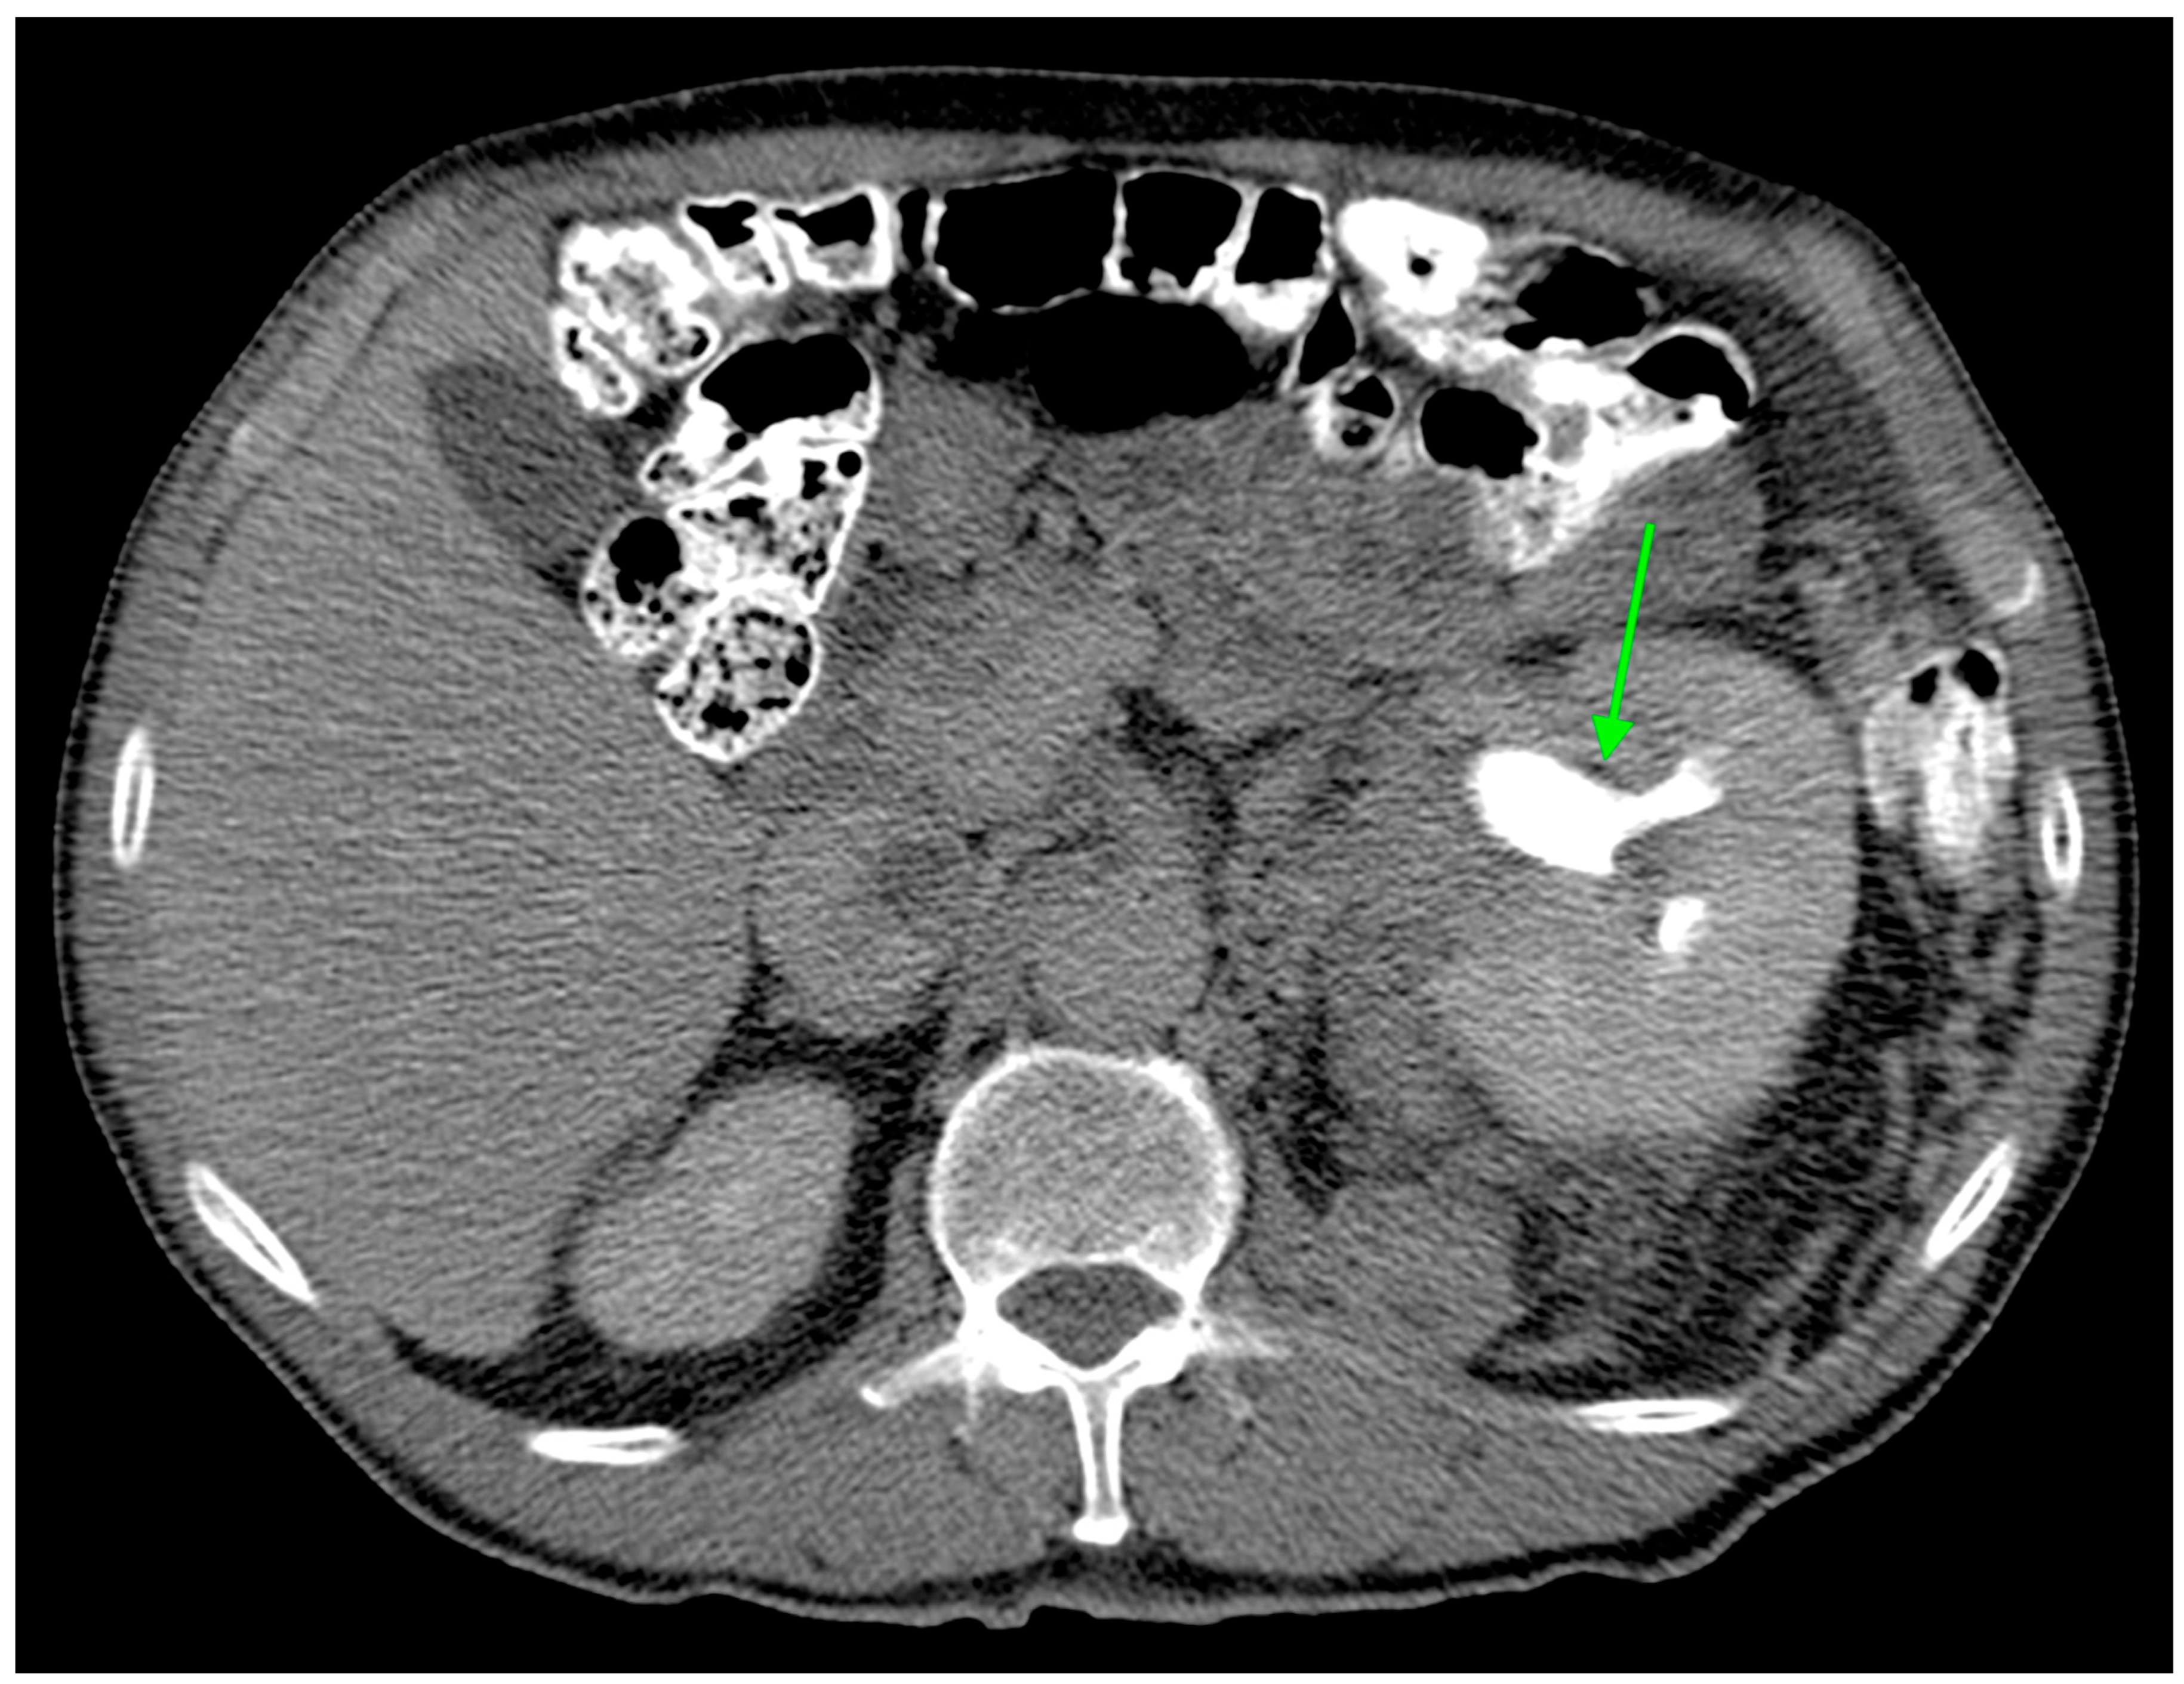

2.3. Lipid Metabolism Imaging Features

| Hydronephrosis | 6 (3.0%) | 4 (8.9%) | 2 (1.3%) | 0.025 |